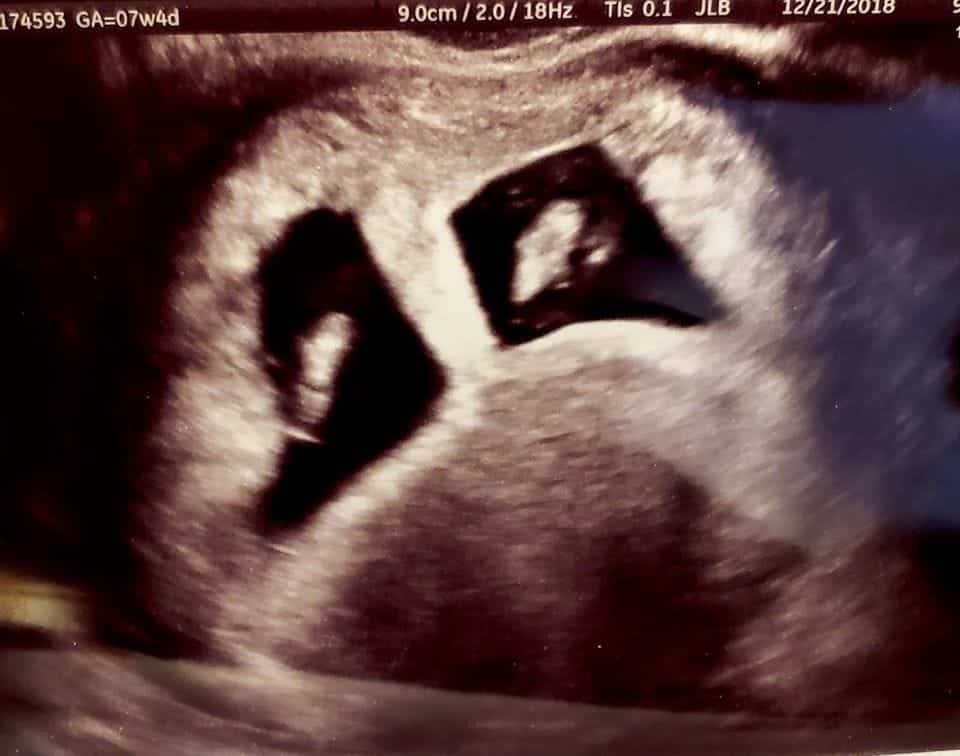

Early Twin Ultrasound at 7 Weeks

The earliest your doctor would likely order an ultrasound confirming twins would be 4 weeks pregnant. But unless you are going through fertility treatments, doing an ultrasound before 6 weeks isn’t very common, with the exception of complications. Women who are going through fertility treatments or have early complications may be able to have an early twin ultrasound at 4 or 5 weeks pregnant and find out they are pregnant with twins.

At four to five weeks after a pregnant woman’s last period the ultrasound commonly shows a small collection of fluid within the lining of the uterus that represents the early development of the gestational sac. At about five and a half weeks after a pregnant woman’s last period the ultrasound typically shows a gestational sac and within it we can see a 3-5 mm bubble-like structure, which is the yolk sac. At approximately six weeks after a pregnant woman’s last period, we can see a small fetal pole, one of the first stages of growth for an embryo, which develops alongside the yolk sac.

Yes! You’d need to have an ultrasound at 7 weeks to confirm a twin pregnancy. Your twin belly at 7 weeks may not look like much of a belly at all, so getting in to your doctor for an ultrasound is key to find out if you’re really having twins.